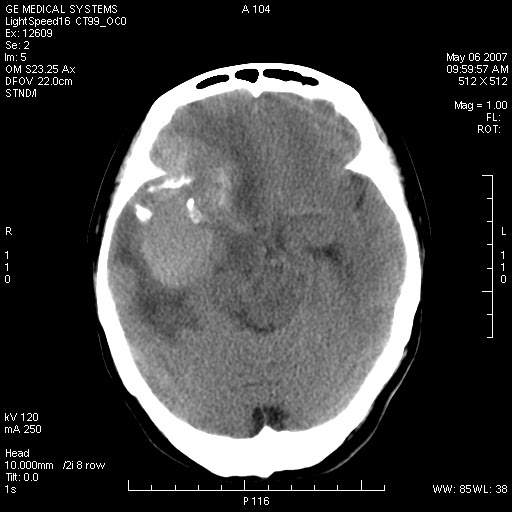

女,60岁,头痛6~7天。

右颞叶巨大高低混杂密度肿块,病灶内可见多发条块状钙化影,占位效应明显,中线结构显著左偏,肿块周围水肿明显,临近颅骨吸收变薄,边缘光整,考虑1少枝胶质瘤2脑膜瘤3转移瘤4室管膜瘤5淋巴瘤6三叉神经瘤(多多益善)合并镰下疝

右额、颞叶巨大高低混杂密度肿块,病灶内可见多发条块状钙化影,占位效应明显,中线结构显著左偏,肿块周围水肿明显,临近颅骨吸收变薄,边缘光整。

考虑:1、少枝胶质瘤;

2、脑膜瘤?

3、镰下疝;

4、建议增强扫描进一步检查。

右额、颞叶巨大高低混杂密度肿块,病灶内可见多发条块状钙化影,占位效应明显,中线结构显著左偏,肿块周围水肿明显,临近颅骨吸收变薄,边缘光整考虑: 1、脑膜瘤;

2、胶母?

4、建议增强扫描进一步检查